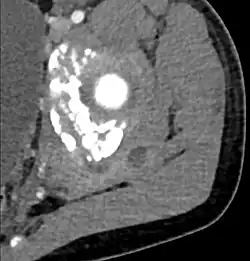

CT with IV contrast showing enlargement and heterogeneous hypodensity in the right pectoralis major muscle. A focal abscess collection with gas within it is present medially. There are enlarged axillary lymph nodes and some extension into the right hemithorax. Note the soft tissue and phlegmon surrounding the right internal mammary artery and vein. The patient was HIV+ and the pyomyositis is believed to be due to direct inoculation of the muscle related to parenteral drug abuse. The patient admitted to being a "pocket shooter" -

CT exam showing a multiloculated fluid collection in the left gluteus minimus muscle found to be a staph aureus pyomyositis in a 12-year-old healthy boy.